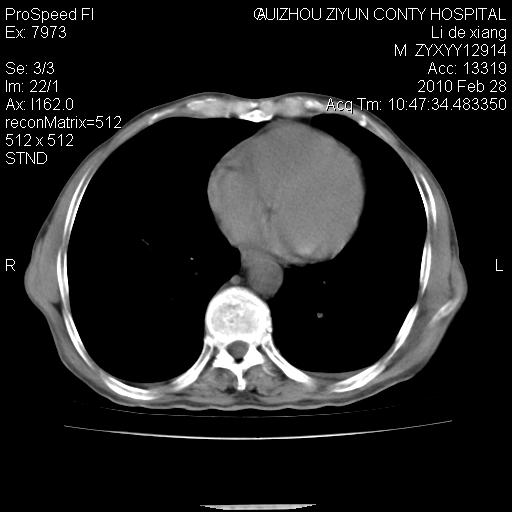

标题: CT24776:男 71Y 咳嗽咳痰胸痛两月,伴声音嘶哑。 [打印本页]

纵膈淋巴结肿大 不除外占位性阻塞

左侧中央型肺癌伴左肺上叶阻塞性肺炎及节段性不张可能性大,建议纤支镜检查!纵隔淋巴结转移.

左侧中央型肺癌伴左肺上叶阻塞性肺炎及纵隔淋巴结转移。

患者有声音嘶哑,若时间长了,没改变,喉镜检查无异常,可考虑左侧喉返神经受累,因为:左侧喉返神经绕主动脉弓或肺动脉韧带的主动脉端,沿气管与食管之间的沟上行至颈部.

支持肺癌.

左上叶支气管狭窄,阻塞性病变,肺门肿块,纵隔及肺门淋巴结增大,中央性肺癌

左肺中央型肺癌并阻塞性改变、纵膈 淋巴结转移